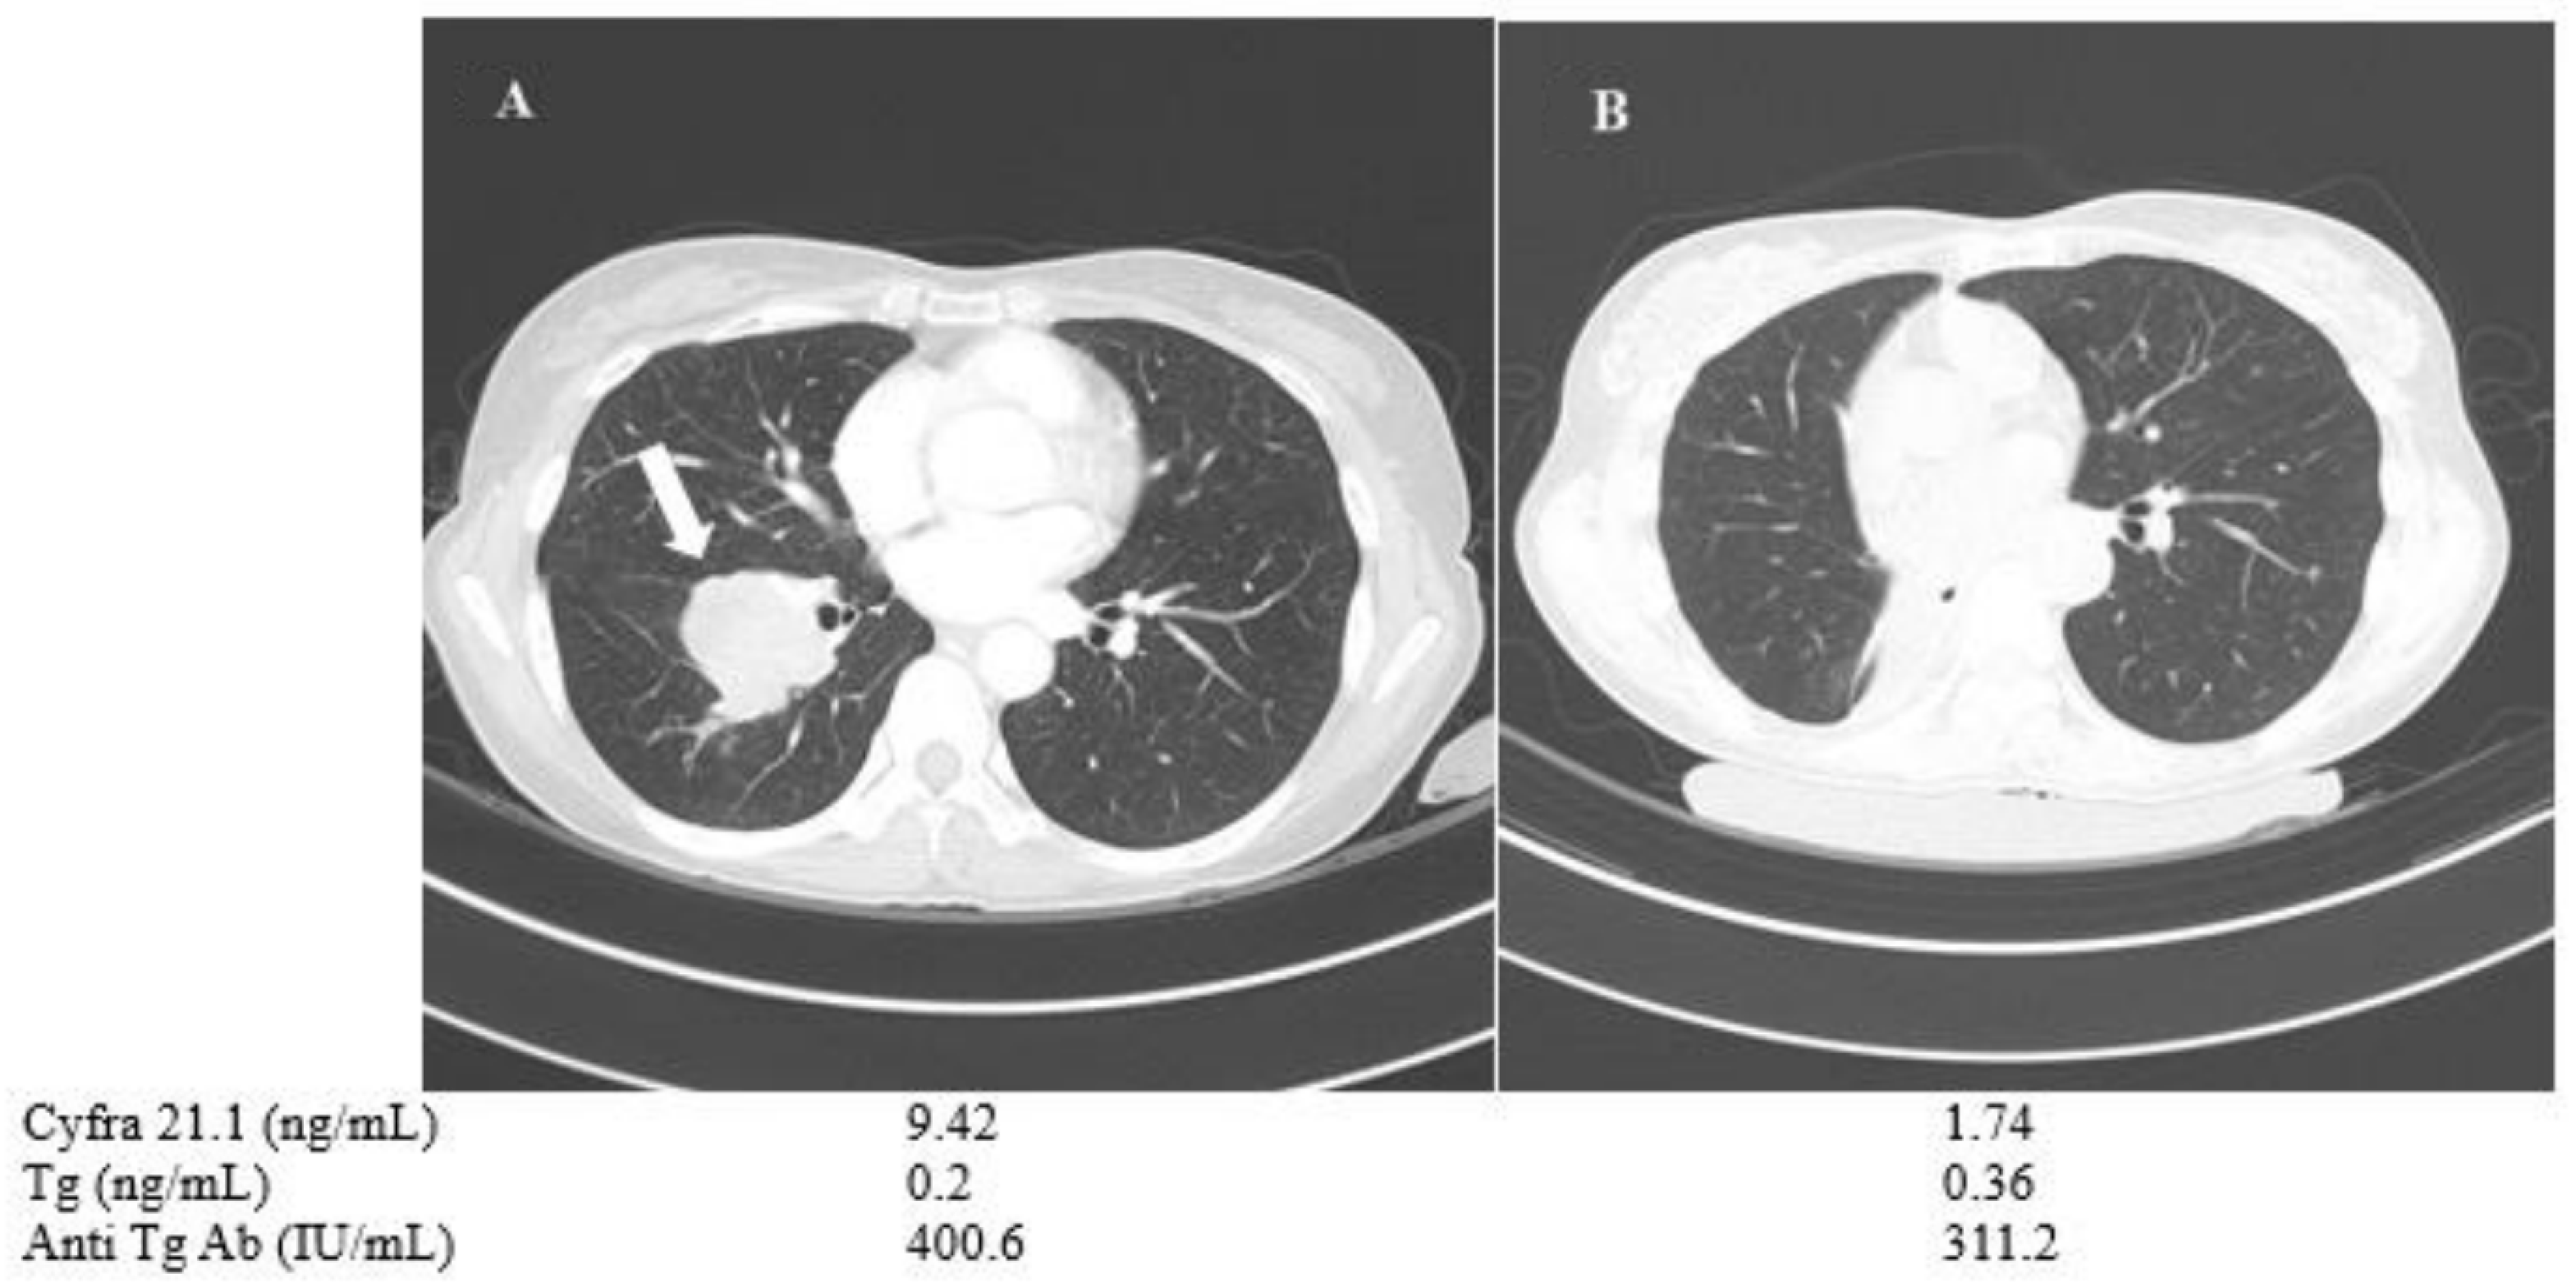

A 50-year-old female (patient no. 8) who had advanced PTC with multiple lung metastases and a single large tumor mass (measuring 4.6 cm in maximal diameter) in the right lung showed low Tg and high anti-TgAb levels, which interfered with follow-up of the disease status based on Tg levels (Figure 5.) During the follow-up, the patient was treated with sorafenib, which resulted in stable disease. However, bilobectomy of right middle and low lobes was done to resect a slow-growing large tumor mass in the right lung, and thereby reduced the tumor burden in pulmonary metastasis. The post-operative pathology confirmed metastatic PTC, and next-generation sequencing revealed BRAF V600E mutation, TERT splicing mutation and EIF3E-RSPO2 gene fusion, indicating de-differentiation and poor prognosis. Surgery decreased the patient’s Cyfra 21.1 level remarkably, whereas Tg and anti-TgAb levels showed little or minor changes (Figure 5).

Figure 5.

Change in chest CT images and serum biomarkers of a 50-year-old PTC female with Anti-Tg Ab (patient No. 8). The patient’s 4.6 cm tumor mass (arrow, A) was removed via bilobectomy of right middle and right low lobes (B).